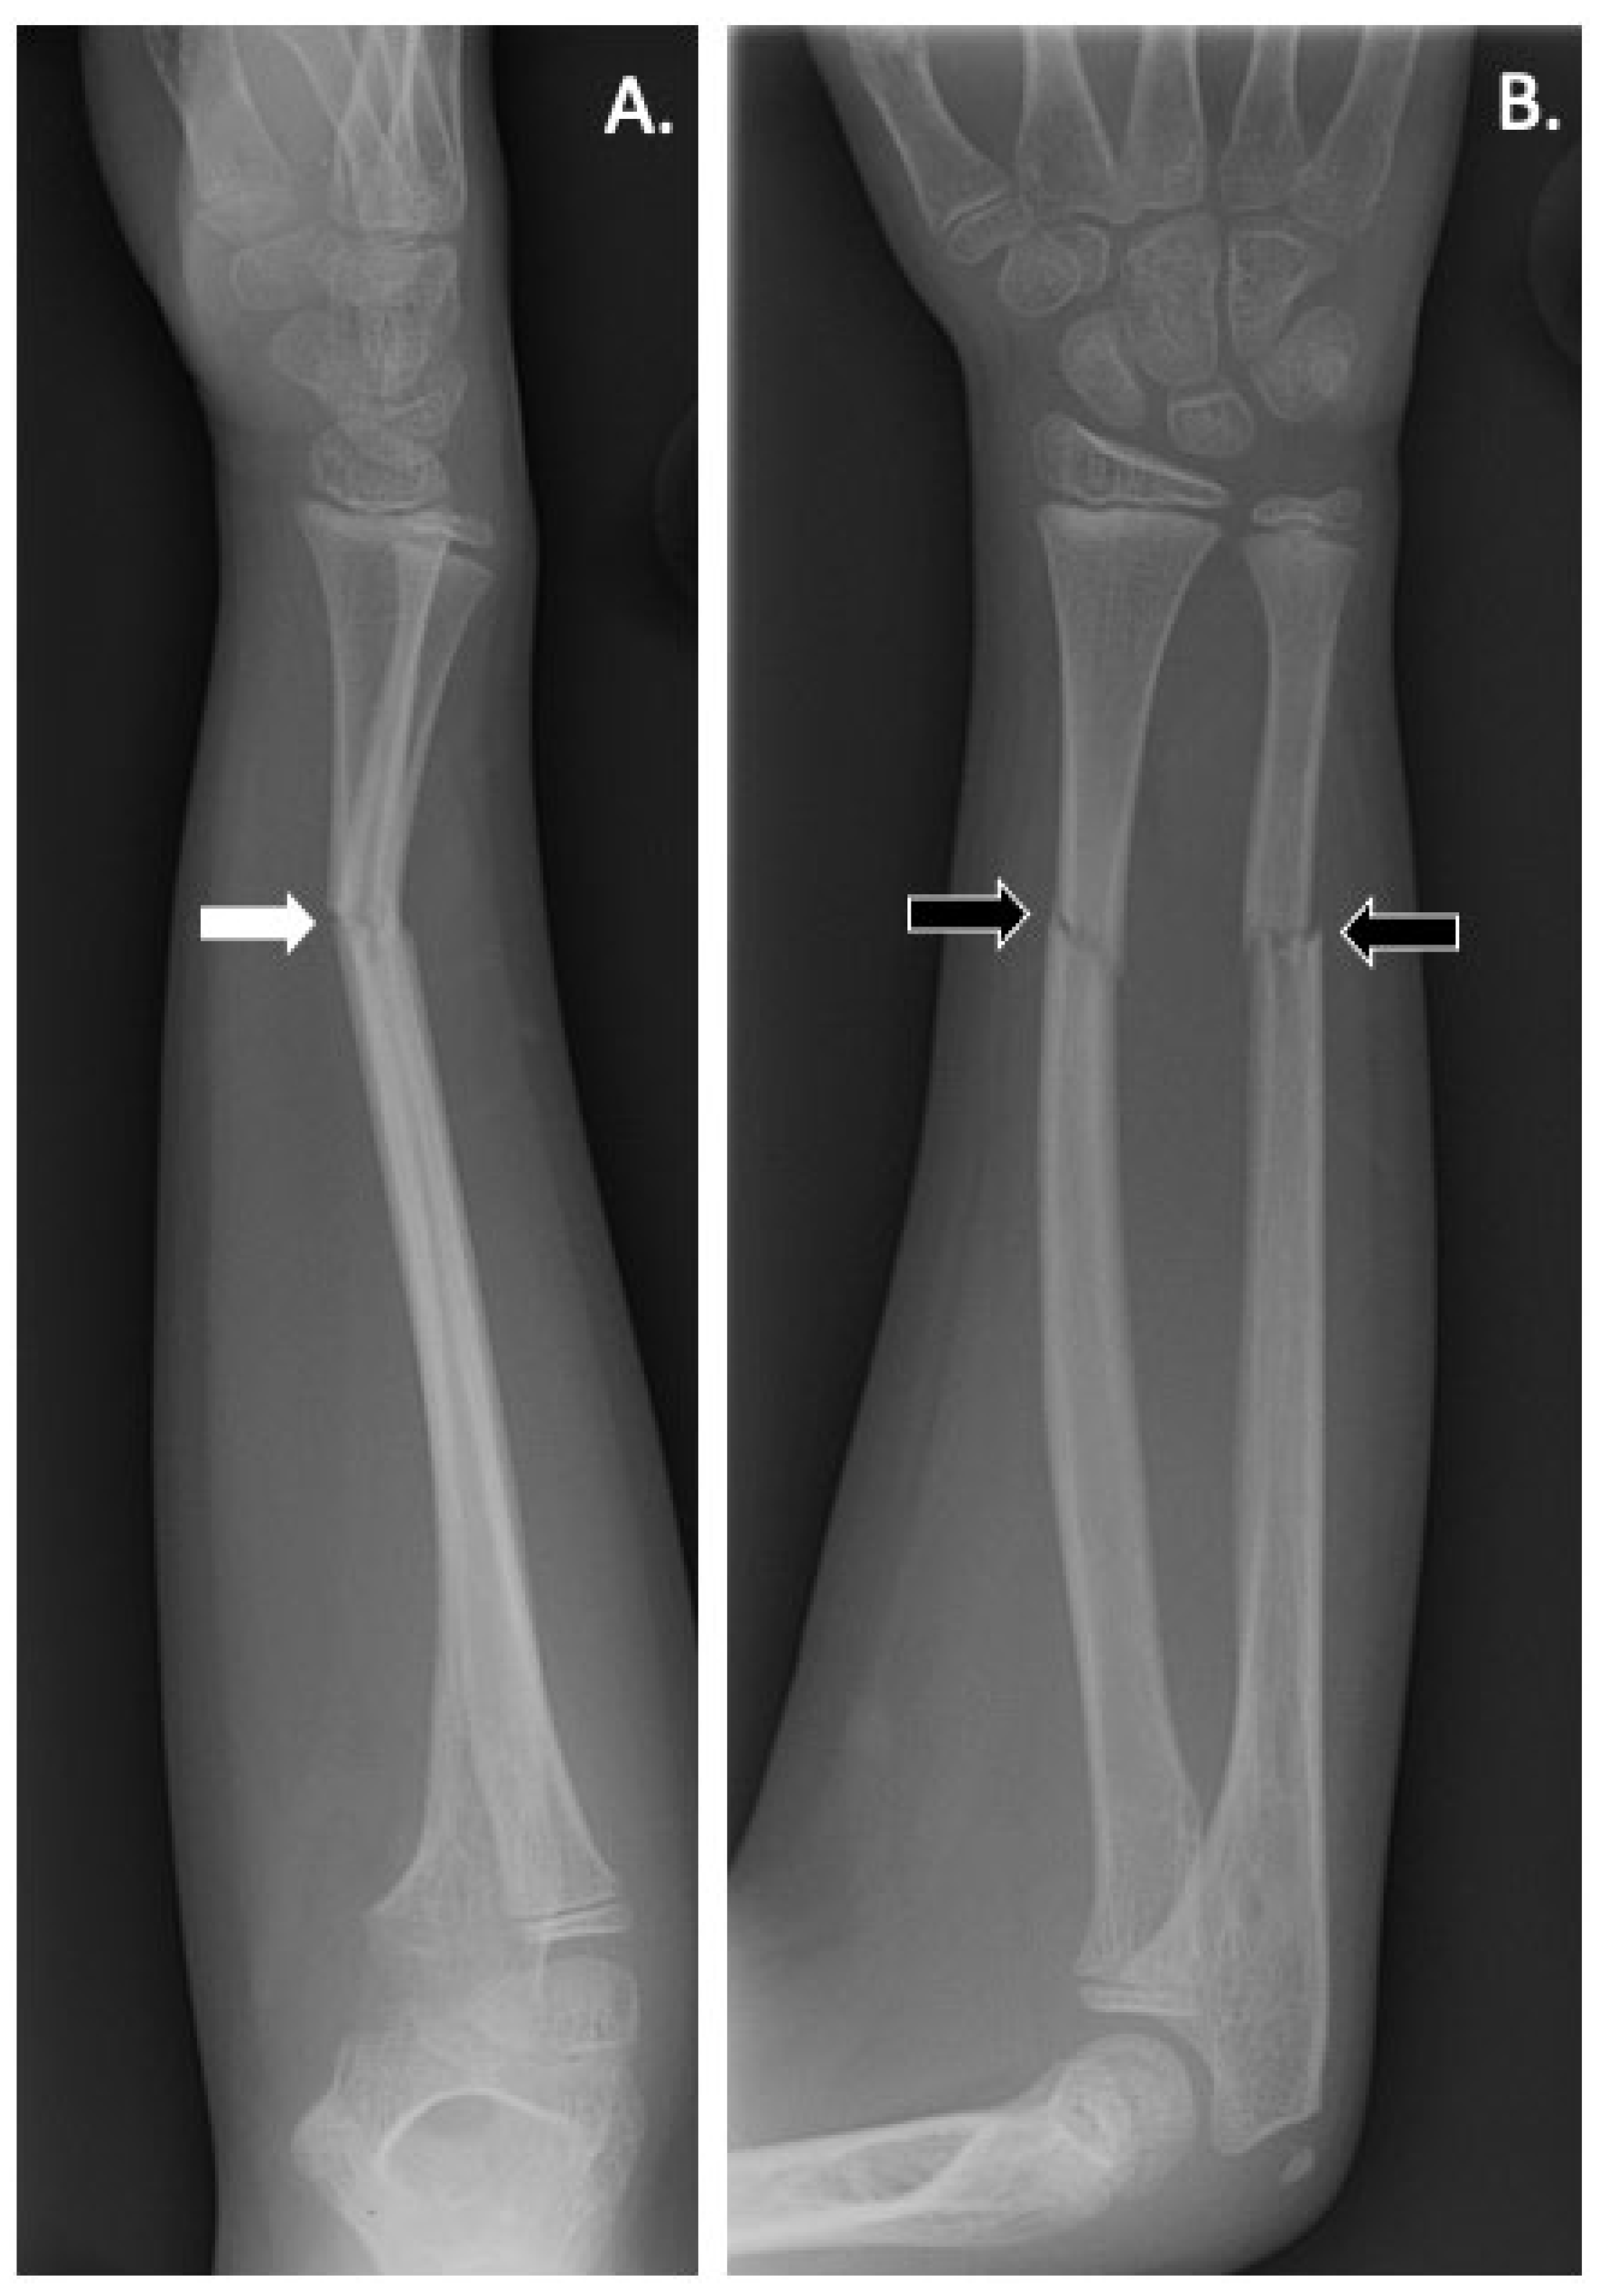

- Littman, J.; Phornphutkul, C.; Saade, C.; Katarincic, J.; Aaron, R. Osteoporosis, Fractures, and Blindness Due to a Missense Mutation in the LRP5 Receptor. Orthop. Res. Rev. 2023, 15, 39–45. [Google Scholar] [CrossRef] [PubMed]